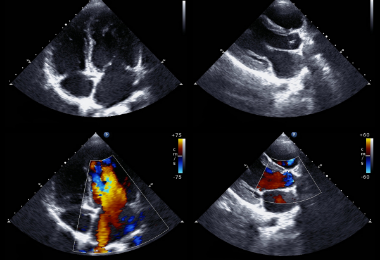

USG serca

Inaczej nazywane ECHO serca. Jest badaniem nieodzownym do podjęcia jakiegokolwiek leczenia kardiologicznego. Dzięki niemu możliwe staje się określenie struktury serca i funkcji zastawek, zaburzeń kurczliwości ściany, przecieków, fal zwrotnych, frakcji wyrzutowej i wielu innych parametrów.

USG dopplerowskie

Służy do oceny przepływu krwi w naczyniach krwionośnych i sercu. Wykorzystuje się tu fakt zmiany długości fali odbitej od przedmiotu, który zbliża się lub oddala od głowicy. W przypadku USG takim przedmiotem są krwinki czerwone. Analizując odbitą od nich falę ultradźwiękową, można wykreślić kierunek i sposób przepływu krwi. Mierząc obszar zmiany barwy, jego kolor i nasycenie, dowiadujemy się np., że: jest nieszczelna zastawka mitralna w sercu; w aorcie znajduje się skrzeplina, która zaburza przepływ krwi, przewód Bottala jest drożny.